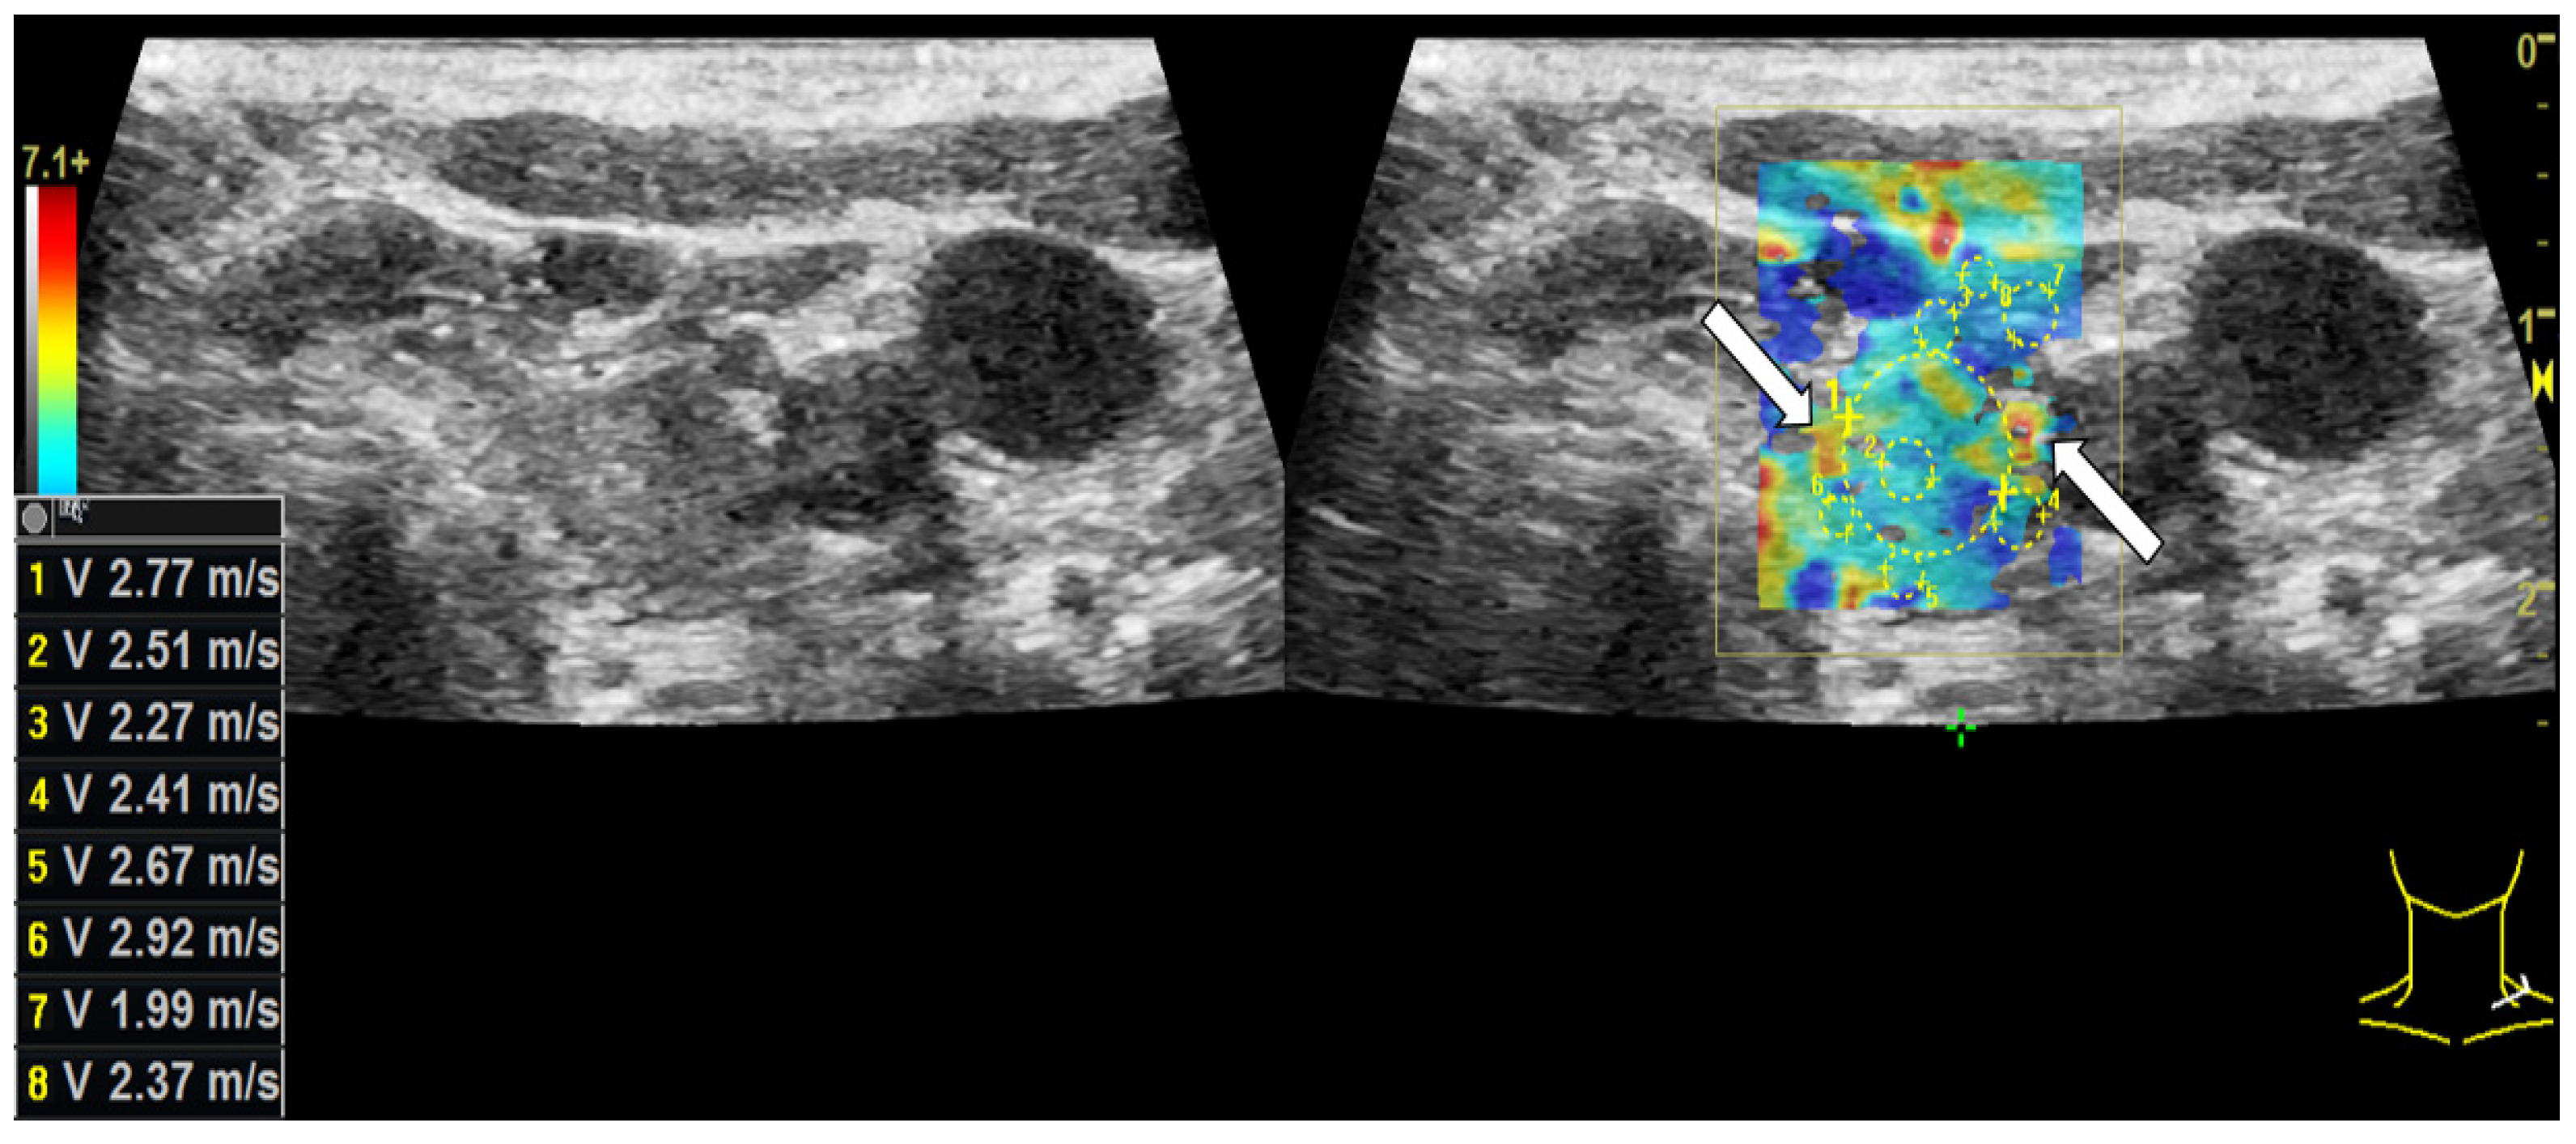

3.2. Shear-Wave Elastography

| Shear-Wave Elastography Measurements | Benign (n ± STD) | Benign (%) | Malignant (n ± STD) | Malignant (%) |

|---|---|---|---|---|

| center [m/s] | 3.50 ± 1.0 | 160.34% | 4.60 ± 1.3 | 226.56% |

| margin [m/s] | 3.49 ± 0.7 | 160.39% | 4.22 ± 1.1 | 207.74% |

| surrounding tissue [m/s] | 2.18 ± 0.8 | 100.00% | 2.03 ± 0.7 | 100.00% |

| center [kPa] | 41.16 ± 25.5 | 260.3% | 69.80 ± 44.8 | 499.61% |

| margin [kPa] | 40.19 ± 14.8 | 254.15% | 60.09 ± 25.1 | 430.16% |

| surrounding tissue [kPa] | 15.81 ± 12.5 | 100.00% | 13.97 ± 6.6 | 100.00% |

| Shear-wave elasto-graphy | marginal cut-off: 4.0 m/s | 90.0 | 3.5 | 75.0 | 81.4 |

| central cut-off: 3.9 m/s | 88.4 | 2.3 | 75.0 | 70.1 | |

| marginal cut-off: 50.7 kPa | 90.8 | 1.1 | 75.0 | 75.3 | |

| central cut-off: 46.9 kPa | 89.2 | 1.0 | 75.0 | 72.2 | |